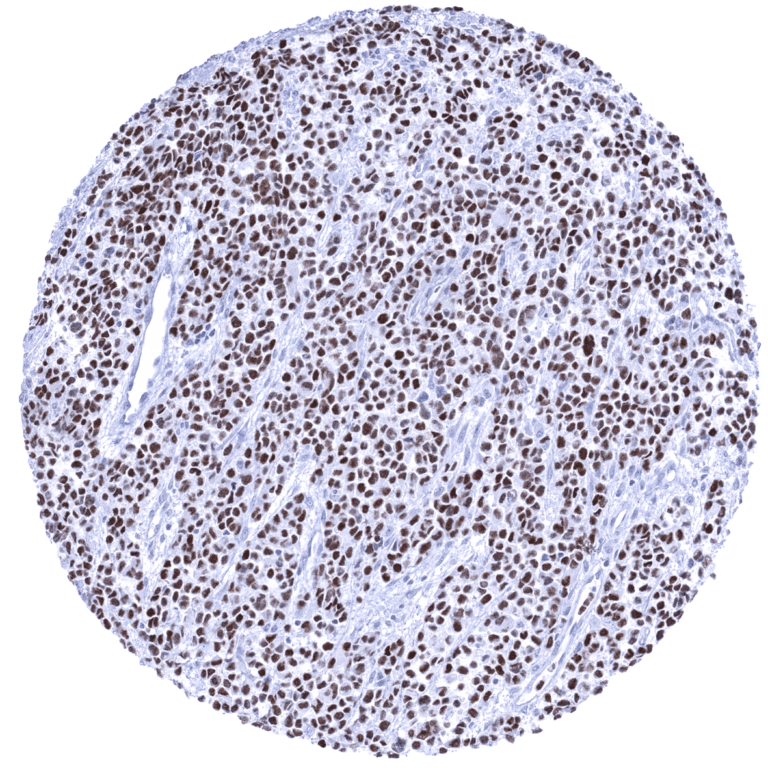

Positive control = Rhabdomyosarcoma with previously documented MyoD1 expression should demonstrate a moderate to strong nuclear MyoD1 immunostaining.

Positive control: Rhabdomyosarcoma with previously documented MyoD1 expression should demonstrate a moderate to strong nuclear MyoD1 immunostaining.

A positive MyoD1 immunostaining is seen in most cases of rhabdomyosarcoma. Rarely, a positive MyoD1 staining can also occur in various other tumor entities such as for example mesenchymal chondrosarcomas or sarcomatoid carcinomas.

Orthogonal validation: For the antibody MSVA-801R orthogonal validation by comparing the normal tissue immunostaining data with data from three independent RNA screening studies, including the Human Protein Atlas (HPA) RNA-seq tissue dataset, the FANTOM5 project, and the Genotype-Tissue Expression (GTEx) project, which are all summarized in the Human Protein Atlas (Tissue expression MyoD1) does result in concordant results. Immunostaining by using MSVA-801R is not seen in skeletal muscle (and tongue) as suggested by RNA expression data. This is not surprising, because of the low level of RNA expression which is unlikely to result in detectable protein expression. True detection of MyoD1 by MSVA-801R is suggested by the strong nuclear positivity seen in 3 of 4 analyzed rhabdomyosarcomas (images of all of these cases are shown in the tumor gallery). Non-nuclear MyoD1 immunostaining is sometimes seen for MSVA-801R in pancreatic acinar cells (granular cytoplasmic) and in mature placenta (membranous, superficial membrane of syncytiotrophoblast). These findings are considered a (tolerable) cross-reactivity.

Comparison of antibodies: That the cytoplasmic and membranous staining of pancreas and placenta by MSVA-801R reflects a cross-reactivity was confirmed by a comparison with another commercial anti-MyoD1 antibody RTU (IVD) showing a different cross-reactivity staining pattern in pancreatic cells and lacking membranous staining in the placenta (see antibody comparison below). The staining for the RTU (IVD) antibody was done by using an autostainer and the recommended protocol.

Antibody Comparison: MSVA-801R vs another commercial anti-MyoD1 antibody RTU (IVD)